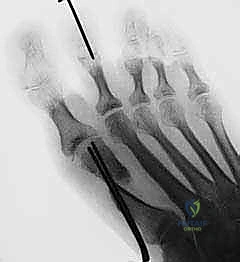

الصورة توضح مفهوم "التصحيح المثالي" لورم إبهام القدم، حيث يتم رسم خط موازٍ للعظم المشطي الثاني يلامس قاعدة العظم المشطي الأول. يساعد هذا التخطيط الدقيق الأستاذ الدكتور محمد هطيف في تحديد مكان ودرجة التحريك اللازمة للعظم المشطي بدقة متناهية.

الدقة هي مفتاح النجاح. يوضح هذا التخطيط كيف يقوم الدكتور هطيف بحساب زوايا القص العظمي بالملليمتر قبل بدء الجراحة لضمان استعادة الميكانيكا الحيوية السليمة للقدم.

تجهيز القدم للعملية الجراحية. يتم رسم خطوط الشق الجراحي بعناية فائقة لتقليل الندبات وضمان الوصول الأمثل للمفصل.